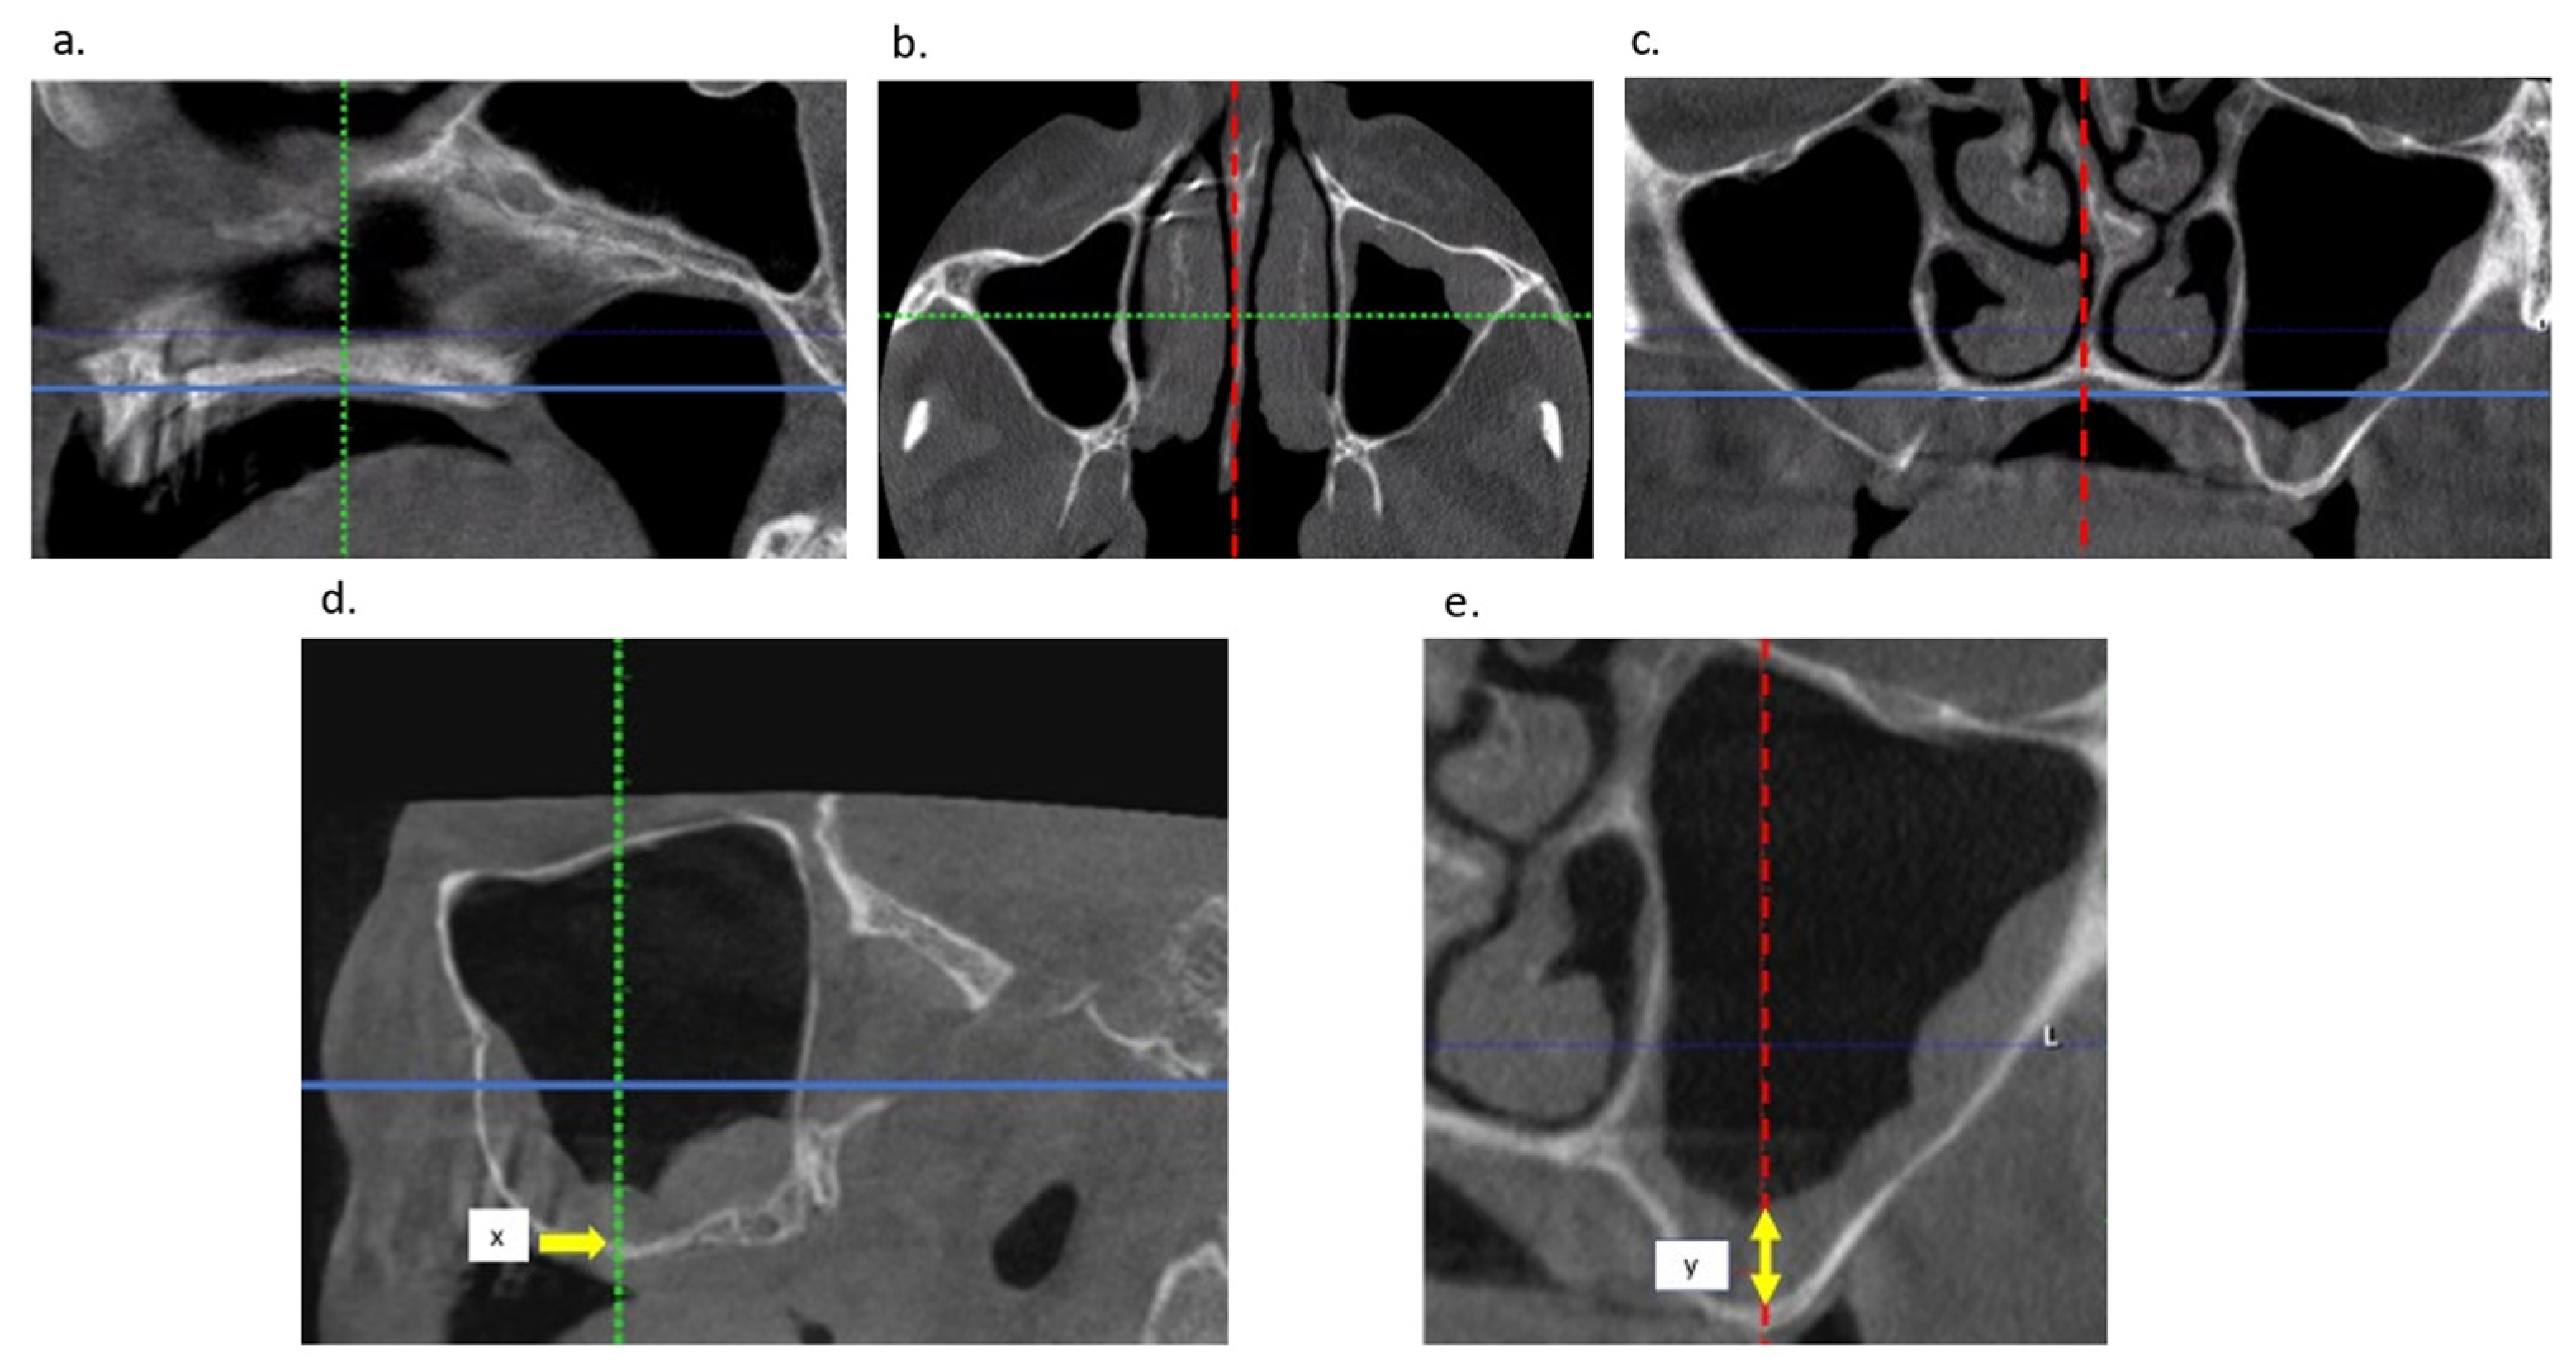

2.2. Radiological Examination